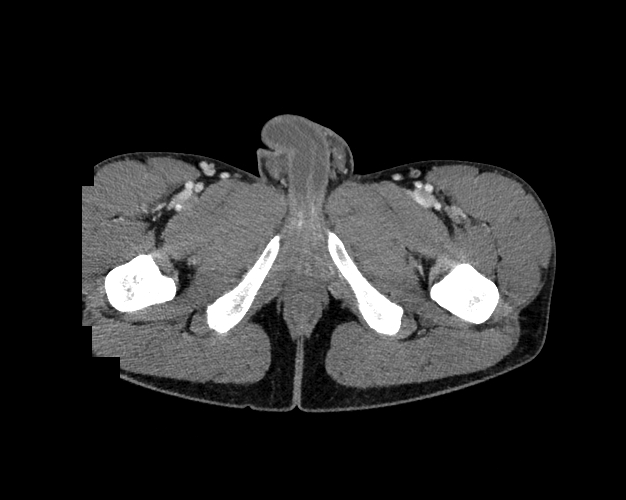

Pelvis

Covers pelvic MRI anatomy.